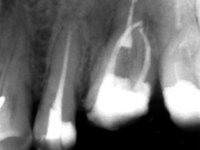

Male patient, 34 years old, non-smoker. Teeth 17 and 16 had extensive restorations with composite resin and placed intra-radicular posts. In the imaging examination, it was found that the endodontic treatment was not technically satisfactory, but had been asymptomatic for several years. The patient was rehabilitated with a 2-element bridge at 17 and 16 and 4 years later an abscess appeared in the apical area of 2.6. It had the 2.8 tooth included with a close relationship with the 2.7 root. During these 4 years there was no positional change of this tooth. After endodontic retreatment of teeth 27 and 26, an abscess appears again in the area of tooth 26, possibly associated with a root fracture. Given the history referred to in relation to tooth 26, it was considered a tooth with indicated extraction.

Teeth 17 and 16 were prepared for the fabrication of a 2-element Zr bridge. The impression was performed with a double mixing technique and a monolithic bridge in Zr was made in the laboratory. 4 years later, an abscess appeared in the apical area of tooth 26. It was decided to remove the bridge, remove the intra-radicular posts and retract the endodontic treatments of teeth 17 and 16. The removal of the bridge was carried out by making two cervical cavities. in the palatal area of the bridge and with a microluxator, disinsertion movements were performed. The intra-radicular posts were removed using fine drills and an ultrasound tip. The bridge was provisionally cemented and the patient was referred to a fellow endodontist for endodontic retreatment. After the retreatment, the intraradicular posts were placed again and the bridge was definitively cemented. One year later, a new abscess appears, possibly related to a root fracture. The bridge was sectioned between tooth 27 and 26 and tooth 26 was extracted and the crown of 27 was provisionally cemented. 3 months later, teeth 27 and 25 were prepared and a temporary bridge was made in dual polymerization resin. Then, an impression was made using the double mixing technique and a 3-element bridge in Zr was made in the laboratory. It was permanently cemented in the mouth with resin-reinforced glass ionomer cement.